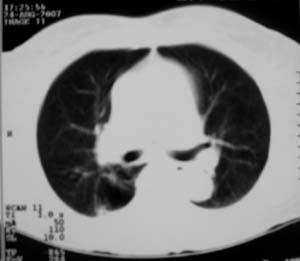

以下是引用zjzjr在2007-8-30 22:22:00的发言:[br]右上肺肺囊肿合并感染.右下肺肺大泡.左肺舌段感染.